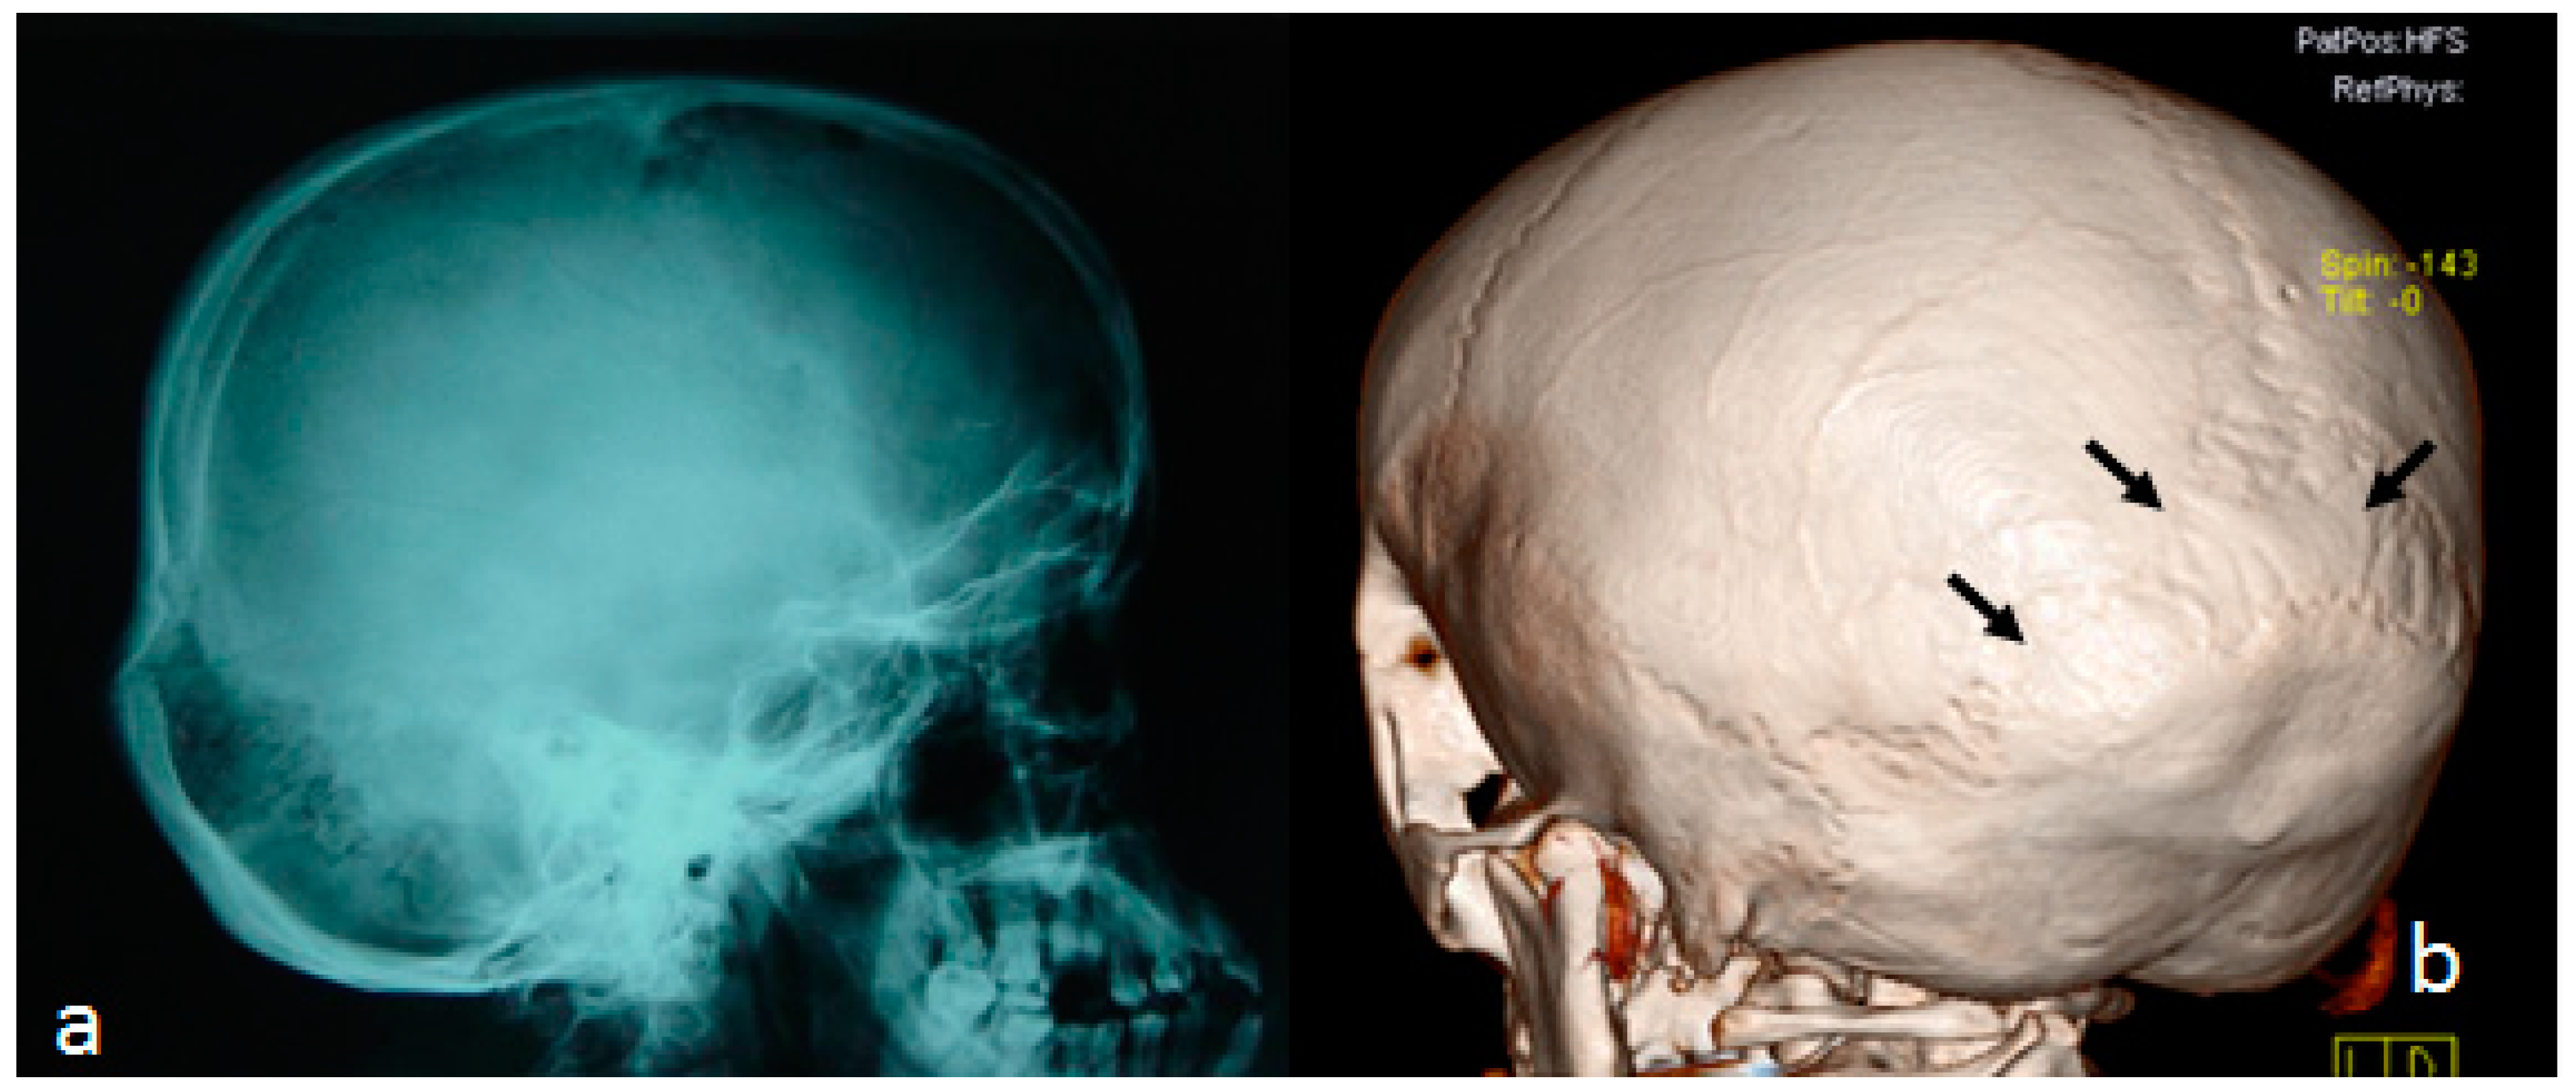

4. Multicentric Carpotarsal Osteolysis Syndrome